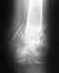

я не вижу снимка, но скажу одно-динамизация нужна, обычно через 7-8 недель,а для того чтобы винт в стержне не сломался после нагрузки на ногу. винт убирается, и разрешается полная нагрузка на конечность. а по поводу остеопороза, он есть потому, что конечность не испытывает должной нагрузки. хотя по правилам без снимка не обсуждают проблему.